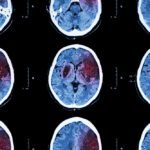

• CT scan of the brain to determine if there is any bleeding

• MRI of the brain to determine the location of the stroke